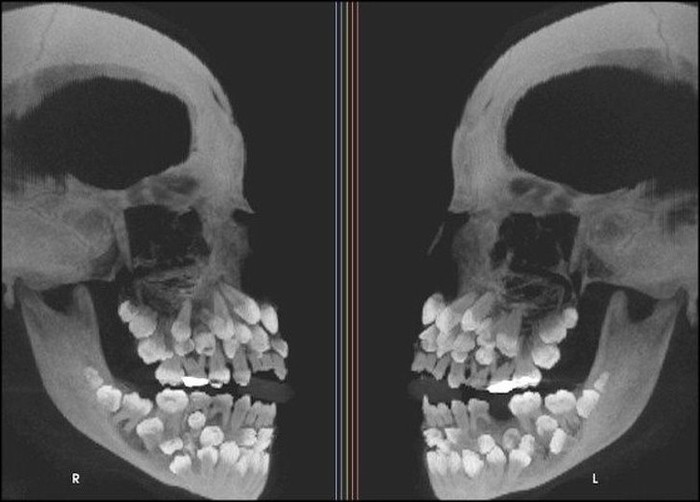

Penampakan seseorang yang mengalami Hyperdontia, merupakan kondisi mulut yang ditandai dengan jumlah gigi yang berlebih, di mana seseorang memiliki lebih dari 20 gigi primer atau lebih dari 32 gigi permanen. (Foto: Brightside)